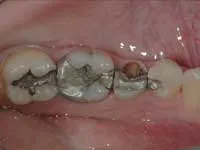

Quality of remaining tooth structure

Assuming that there is a significant amount of coronal tooth structure remaining, the quality of the remaining tooth structure should be considered. Often, remaining tooth structure has discolored areas, slightly demineralized areas, cracks, undermined areas, or other negative characteristics. Removal of tooth structure with these characteristics allows a realistic and necessary appraisal of the amount of viable tooth structure remaining. After removing the affected areas, the same suggestions stated in the previous section on quantity of tooth structure remaining apply. Posts are often indicated.